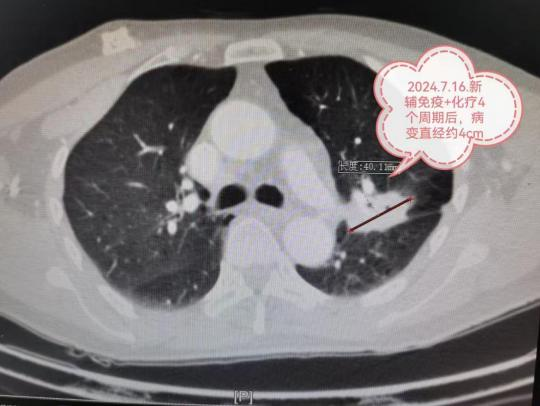

近日,贵州航天医院心胸外科、麻醉科团队成功开展Tubeless单孔胸腔镜肺切除术,术中患者在麻醉下保持自主呼吸,无需进行气管插管。术后,患者在医务人员和家属的搀扶下走回病房,自述仅有轻微痛感,如同做了一次无痛胃镜一样。 案例分享 患者廖先生因咳嗽伴胸部疼痛前来我院就诊,在为患者完善胸部CT检查后,发现患者存在右上肺结节,高度怀疑为恶性肿瘤,呼吸与危重症医学科、心胸外科、麻醉科等科室当即对患者情况进行多学科讨论(MDT),为患者制定了Tubeless单孔胸腔镜肺楔形切除手术方案,在充分征得患者及其家属同意后,手术按计划顺利实施。 术中患者仅插入喉罩,保留了自主呼吸,仅仅使用镇静药和镇痛药并辅以区域神经阻滞,未使用肌松药。手术结束时,廖先生即刻清醒并拔出喉罩,经PACU复苏观察后,由医务人员和家属扶着走回了病房。 术后第二天,患者出院时惊讶的说道:“这个技术真的很神奇,病房里的病友做的其他类型的肺切除手术,他们连床都下不了,我却轻松这么多,手术后都是自己走回的病房,也没感觉到有多痛,像做了一次无痛胃镜一样”。 Tubeless科普小知识 传统胸外科的手术需要在大剂量镇静、镇痛、肌松药等全身麻醉下,实施双腔支气管插管来进行单肺正压通气,但气管插管所用的粗大双腔管可能会造成声带及气管损伤,引起咽喉部疼痛、咳嗽、气道异物感等术后呼吸道及肺部相关并发症。Tubeless技术也叫“无管技术”,是一种在加速康复外科(ERAS)理念指导下的全新的麻醉技术,与传统的双腔支气管插管全麻胸外科手术不同,在整个手术过程中,不需要进行气管插管,仅需使用喉罩,保留了患者自主呼吸,麻醉使用静脉复合辅以区域阻滞麻醉,减少50%阿片类镇痛药物的使用,几乎不使用肌松药。 气管插管 非气管插管 与传统胸外科手术比较,Tubeless技术能最大限度减少双腔支气管全麻带来的并发症,包括减少呼吸机正压通气可能造成的压力性肺损伤、术后低氧血症发生率、患者气道损伤和咽喉部不适;此外,麻醉药物用量的减少,可以避免术后恶心呕吐、再灌注损伤、血栓形成、术后认知功能障碍、四肢和消化系统肌肉无力等副作用出现。简而言之,就是以更小的气道应激反应和最小的气道损伤实现精准麻醉,加速患者术后康复进程。 Tubeless胸外科手术一方面可以使患者更快恢复咳嗽排痰能力,减少肺部并发症,加快康复,提高生活质量;另一方面由于麻醉药用量、住院时间等的减少,患者因治疗产生的费用也会相应减少,在一定程度上减轻患者及家庭的经济负担。 注:图片来源于网络,如有侵权,请联系删除。 贵州航天医院Tubeless单孔 胸腔镜专家团队 陈光春 心胸外科主任 副主任医师 原部队军医,曾工作于陆军军医大学附属大坪医院。中国医师协会手汗症专委会全国委员,重庆市中西医结合学会胸外科专委会常务委员,重庆市医学会微创专委会胸外科学组委员,重庆市医药生物技术协会肺癌、食管癌防治专委会委员。 专业擅长:从事临床工作近30年,对食管癌、食管裂孔疝、反流性食管炎、肺结节、肺癌、血气胸、脓胸、纵隔肿瘤、重症肌无力、手汗症、胸部外伤等的诊疗有丰富的临床经验;擅长电视胸腔镜肺癌根治术、食管癌根治术、纵膈肿瘤切除术等微创手术;特别擅长单孔胸腔镜微创手术、3D-技术引导下肺段、亚段切除术等最先进的微创技术;手汗症微创手术治疗成功吸引全国10多个省约300名患者慕名前来就诊。 李光才 麻醉科主任 主任医师 专业擅长:对围术期麻醉操作和管理及疑难危重病人的麻醉处置具有丰富的临床经验。 中国心胸血管麻醉学会(CSCTVA)创新与推广分会全国委员;贵州省麻醉学分会委员,贵州省麻醉质控中心委员,遵义市麻醉学分会副主任委员,遵义市医疗事故鉴定专家。毕业于遵义医学院,曾先后到四川大学华西医院、重庆医科大学附属医院、遵义医科大学附属医院的麻醉科培训学习。主持多项新技术、项目的临床应用,主持省部级科研课题一项,并顺利结题。发表论文10余篇。 王 勇 麻醉科教研室主任 主任医师 专业擅长:从事临床麻醉及疼痛诊疗工作约20余年,擅长急危重患者、疑难病例的麻醉和超声引导下血管穿刺及神经阻滞;对颈椎病、腰椎源性疼痛、肩周炎、骨性关节炎、筋膜炎、带状疱疹后遗神经痛、三叉神经痛等慢性疼痛以及顽固性失眠等的超声引导下精准可视化治疗具有丰富的临床经验。 中国疼痛康复产业技术创新联盟专家委员会委员,中国中医药信息学会疼痛学分会常务理事,遵义市医学会麻醉学分会第五届委员会委员,曾到湘雅医院和华西医院进行临床麻醉专项培训,参加“黔医人才计划”到北京宣武医院学习疼痛治疗。主持和参与市级科研3项,参编论著1部,参与在各种核心期刊上发表论文10余篇。 梁 菁 麻醉科 主治医师 临床擅长:擅长老年及小儿手术麻醉,心胸外科手术麻醉,机器人手术麻醉。 毕业于重庆医科大学麻醉专业,2021年于中国人民解放军总医院完成麻醉规范化培训。 贵州航天医院心胸外科简介 心胸外科现有副主任医师2名,医学硕士4名。科室团队擅长电视胸腔镜肺癌根治术、电视胸腔镜食管癌根治术、电视胸腔镜纵膈肿瘤切除术等大型胸外科微创手术,设计并开展了西南地区首例经左胸单孔辅助腹腔镜胃食管交界部癌微创手术;手汗症微创手术治疗在全国有较大影响力,是中国医师协会手汗症专委会全国委员级别单位,吴阶平医学基金会交感神经外科专委会全国委员级别单位,已为全国10余个省、直辖市、自治区患者成功进行手术。并在食管癌、食管裂孔疝、反流性食管炎、肺结节、肺肿块、肺癌、血气胸、脓胸、纵隔肿瘤、胸腺瘤、重症肌无力、手汗症、胸部外伤等胸外科疾病的诊疗方面有着丰富的临床经验。 • ✦ 专科特色 ✦ • (一)单孔胸腔镜技术 相比传统开胸手术以及很多医院的3孔或4孔胸腔镜手术,我科仅行1个孔的单孔胸腔镜手术,创伤更小、疼痛更轻。 传统开胸 4孔胸腔镜 3孔胸腔镜 单孔胸腔镜(我科) (二)3D技术引导下亚肺叶精准微创切除术 3D技术在医学的应用,使精准医学变为可能。如图:右上肺9个结节,3D技术引导下,单孔胸腔镜RS2段切除+流域法RS1bi+RS3bi联合亚亚段切除,将9个肺结节一网打尽。如果没有3D技术指引,该患者只能被迫切除整个右肺上叶,而在3D技术指引下仅切除右肺上叶1/3左右。 (三)新辅助治疗后的肺癌微创根治术 偏晚期的肺癌手术机会渺茫,新辅助治疗(术前免疫、靶向、化疗等)可让患者重获根治性手术机会。如图:7.7cm左上肺癌,若直接手术,可能无法切除或被迫切除左全肺。新辅助免疫+化疗4个疗程后,病变由7.7cm缩小到4cm,在单孔胸腔镜下肺动脉成形完成左上肺癌根治术(左上肺叶切除+淋巴结清扫),不仅只切除了左上肺保留住了左下肺,而且术后病理检查显示术前用药后残存癌细胞比例仅残存6%,也就是说4cm肿块里面94%的组织已经没有癌细胞,远期疗效更佳。 (四)新辅助治疗后的胸腔镜微创食管癌、贲门癌根治术 与肺癌类似,偏晚期的食管及贲门癌手术机会渺茫,因为有了新辅助治疗(术前免疫、靶向、化疗等)而重获根治性手术机会。如图:中段食管癌,病变与周围血管等关系紧密,直接手术估计很难完整切除。3个疗程新辅助免疫+化疗后病变明显缩小,行颈胸腹切口胸腹腔镜联合微创手术后治愈。 (五)经剑突下胸腔镜前纵隔肿瘤切除术 前纵隔肿瘤传统手术需全胸骨劈开,创伤大且疼痛剧烈。我科多采用剑突下胸腔镜手术,创伤小,疼痛轻微。如图:26岁女性,前上纵隔畸胎瘤,最大直径约7CM,与周围大血管关系紧密,经剑突下单孔胸腔镜手术成功切除。 (六)手汗症微创手术 作为中国医师协会手汗症专委会全国委员级单位,参与全国手汗症诊疗技术优化及质量控制专家共识编写,手汗症微创手术治疗在全国有一定影响力,吸引全国各地患者慕名来院手术。 • ✦ 诊疗范围 ✦ • 贵州航天医院麻醉科简介 贵州航天医院麻醉科现有专业技术人员55人,其中高级职称11人。科室有手术间14间,分A、B两个区,每个手术间都配备有高级麻醉机、多参数麻醉监护仪等设备。 • ✦ 专科特色 ✦ • (一)支气管内麻醉下的大容量双肺灌洗术 2008年,在贵州省内率先开展了支气管内麻醉下的大容量双肺灌洗术以治疗尘肺和蛋白沉积症等疾病,并取得了良好的经济效益和社会效益。 (二)自体血回输技术 2015年,开展了自体血回输技术,这个技术的开展,为抢救危重患者争取了宝贵的时间,减少了输异体血的风险。 (三)超声引导下的穿剌技术 2016年 开展了超声引导下的神经阻滞技术和中心静脉穿刺术,此技术的开展,为可视化麻醉打下了基础,同时也大大减少因盲目穿刺给患者带来的痛苦和风险。 (四)小儿先天性心脏疾病手术麻醉 (五)高频通气麻醉硬质气管镜下气道内各种手术及喉罩下各种治疗麻醉 (六)各种慢性疼痛的诊疗 冲击波治疗 银质针巡检 颈神经根脉冲射频调节术 DSA下的椎间盘胶原酶溶解术 • ✦ 诊疗范围 ✦ • (一)手术室内:除了常规手术的麻醉外,我科还开展了胸外科腔镜下肺癌食道癌根治术;泌尿外科腔镜下肾癌、前列腺癌、膀胱癌根治术;骨科髋关节、膝关节置换手术;神经外科颅内肿瘤切除术;肝胆外科左右肝切除、胰头癌根治术;普外科腔镜下结肠癌、直肠癌根治术;妇科宫颈癌、卵巢癌根治术;重症产科等大型四级手术的麻醉。 (二)手术室外: 1.气管镜室:与呼吸与危重症科合作,开展了高频通气麻醉硬质气管镜下气道内的各种手术及喉罩下各种治疗的麻醉,以及无痛纤支镜。 2.DSA:一是与心内科合作,开展了房(室)间隔缺损等介入手术的麻醉(主要是小儿先心病的治疗);二是与神经内外科合作,开展了颅内动脉瘤栓塞术的麻醉;三是与肝胆外科合作,开展了无痛ERCP。 3.胃肠室:与消化内科合作,开展了无痛胃肠镜;。 4.人流室:与妇科合作,开展了无痛人流。 5.产科:与产科合作,开展了无痛分娩。这些在手术室外开展的麻醉技术,为广大的人民群众提供了舒适、无痛、安全的麻醉服务。 (三)麻醉门诊:为手术室外的日间手术患者、无痛胃肠镜、无痛人流等患者提供手术及治疗前的麻醉评估,充分保障了这些患者的医疗安全。 (四)疼痛门诊: 1.各种慢性疼痛的治疗服务:主要有冲击波治疗、臭氧治疗、超声引导下的神经阻滞治疗等。 2.开展的三级手术:经皮穿剌超声引导下胸神经背根神经节、颈神经根脉冲射频调节术。 3.开展的四级手术:椎间盘胶原酶溶解术。 END